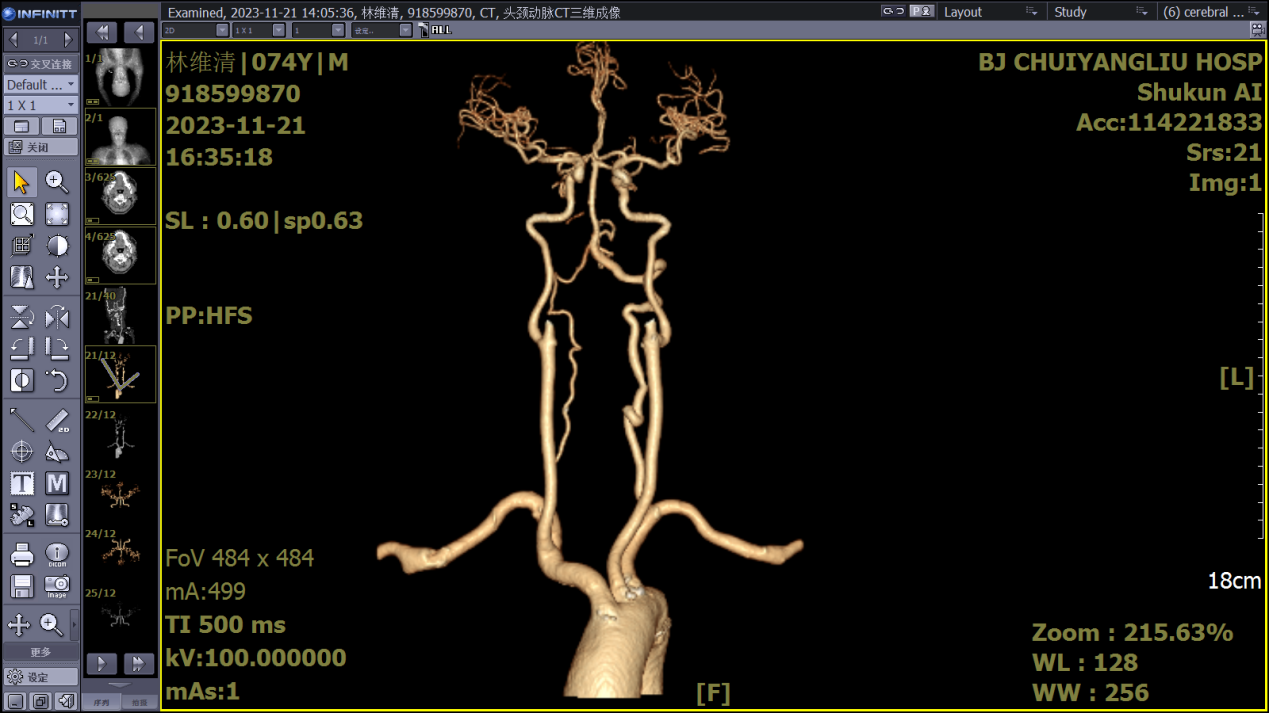

四、CTA和CTP

是一种介入检测方法,原理是显影剂被注入到血管里,因为X光穿不透显影剂,从而可显示出血管影像。CT血管成像(CTA)指静脉注射含碘造影剂后,经计算机对图像进行后处理,可以同时显示血管及骨性结构,清晰显示三维颅内血管系统,对狭窄或闭塞血管可提供重要的诊断依据。